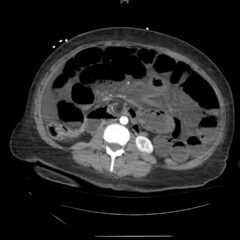

Aortoiliac occlusive disease (AOD) is a manifestation of peripheral arterial disease characterized by stenosis or occlusion of the distal aorta and iliac vessels. Advanced disease may present with symptoms of claudication to the buttock and thighs, erectile dysfunction, and absent or diminished femoral pulses bilaterally. Here, we discuss a case of a 71-year-old male who presented with acute bilateral lower extremity pain and weakness. Pulses were undetectable bilaterally at the groin prompting emergent imaging and vascular surgery consultation due to the suspected diagnosis of AOD. The patient was taken for bilateral femoral artery cut downs with embolectomy. The patient made an impressive recovery with preservation of motor function of lower extremities. In this case report we discuss pertinent workup and management of a patient suspected to be suffering from AOD.